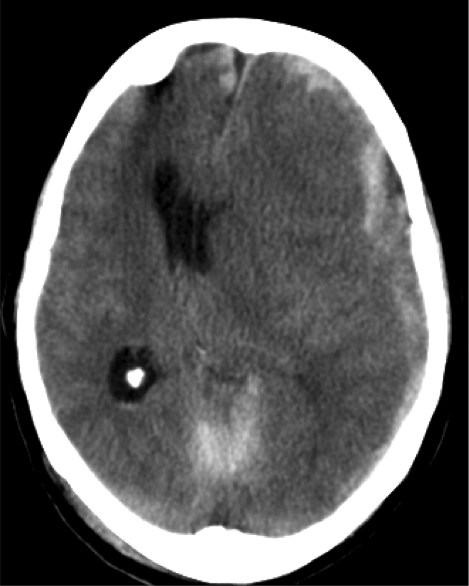

Subfalcina:

- Se produce la herniación de la circunvolución del cíngulo a través de la hoz.

- Puede producir compresión del asta y atrio del ventrículo ipsilateral.

- El VL contralateral puede dilatarse por obstrucción del agujero de Monro.

- Infartos del territorio anterior por compresión de la ACA y venas profundas.